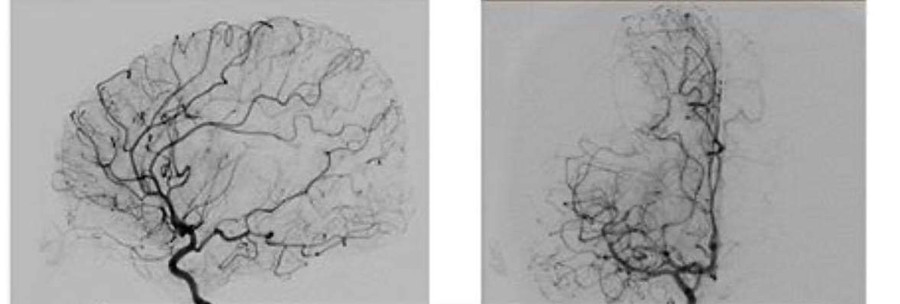

Bệnh nhi bị tắc 1 nhánh của động mạch não giữa bên phải.